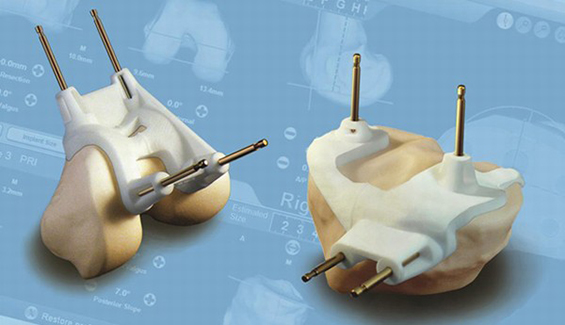

— Our Services

We Provide Exclusive Service

— Our Product

Take a Look at Our Awesome Gallery